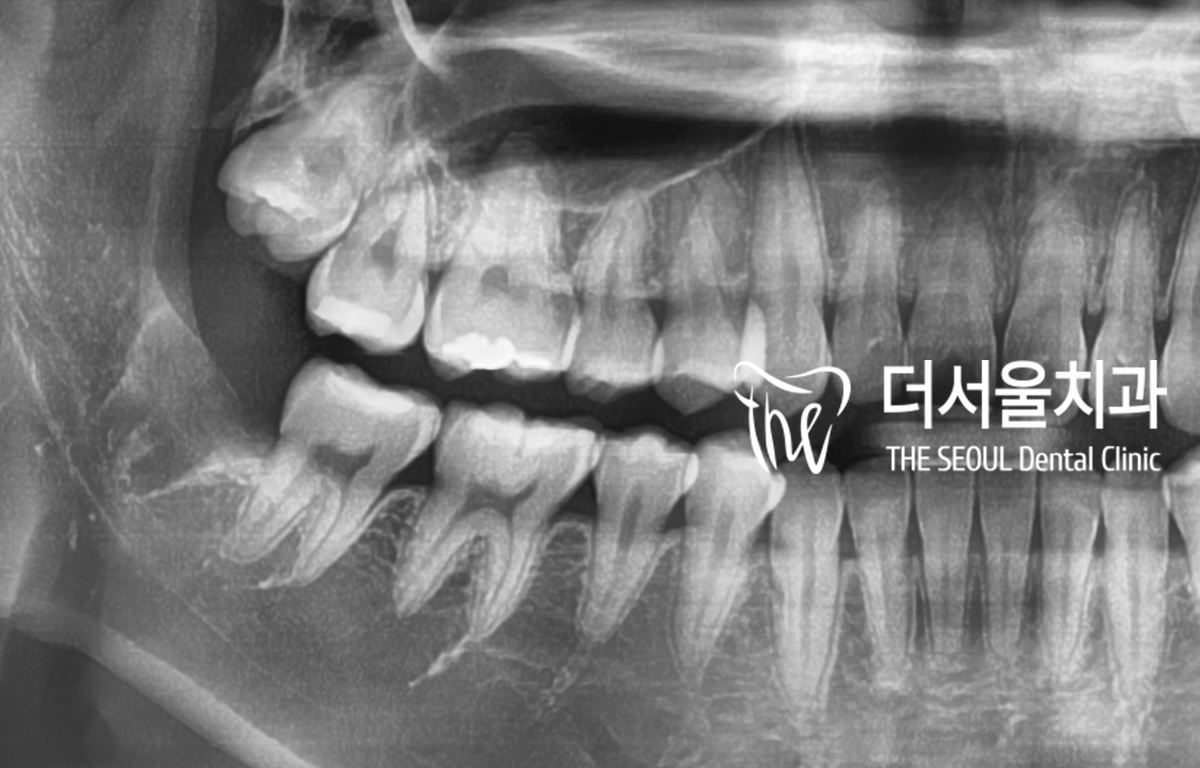

성남치과 환자의 초진 엑스레이를 보면

옆 치아와 거의 붙어 있었으며

신경관과 가까운 뿌리를 확인할 수 있었습니다.

완전매복사랑니 에 신경관과 가깝다..

이건 꽤 고난이도의 수술에 해당되네요.

CT 촬영을 통해

좀 더 자세히 관찰을 했습니다.

다행히 약 2mm 정도 떨어져 있었습니다.